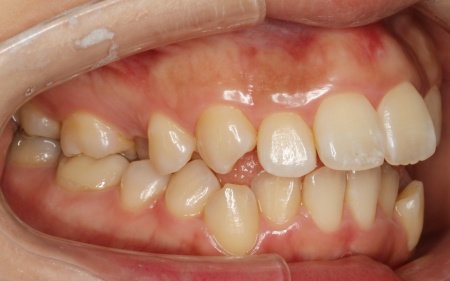

拝見したところ、上下の歯が正しく並ぶためのスペースが足りず、デコボコに生えていました。

とくに、犬歯が正しい歯並びから大きく飛び出した位置に生えており、いわゆる八重歯の状態です。

また、奥歯を噛み合わせた際に上下前歯が噛み合わず隙間ができる開咬(かいこう)も認められました。